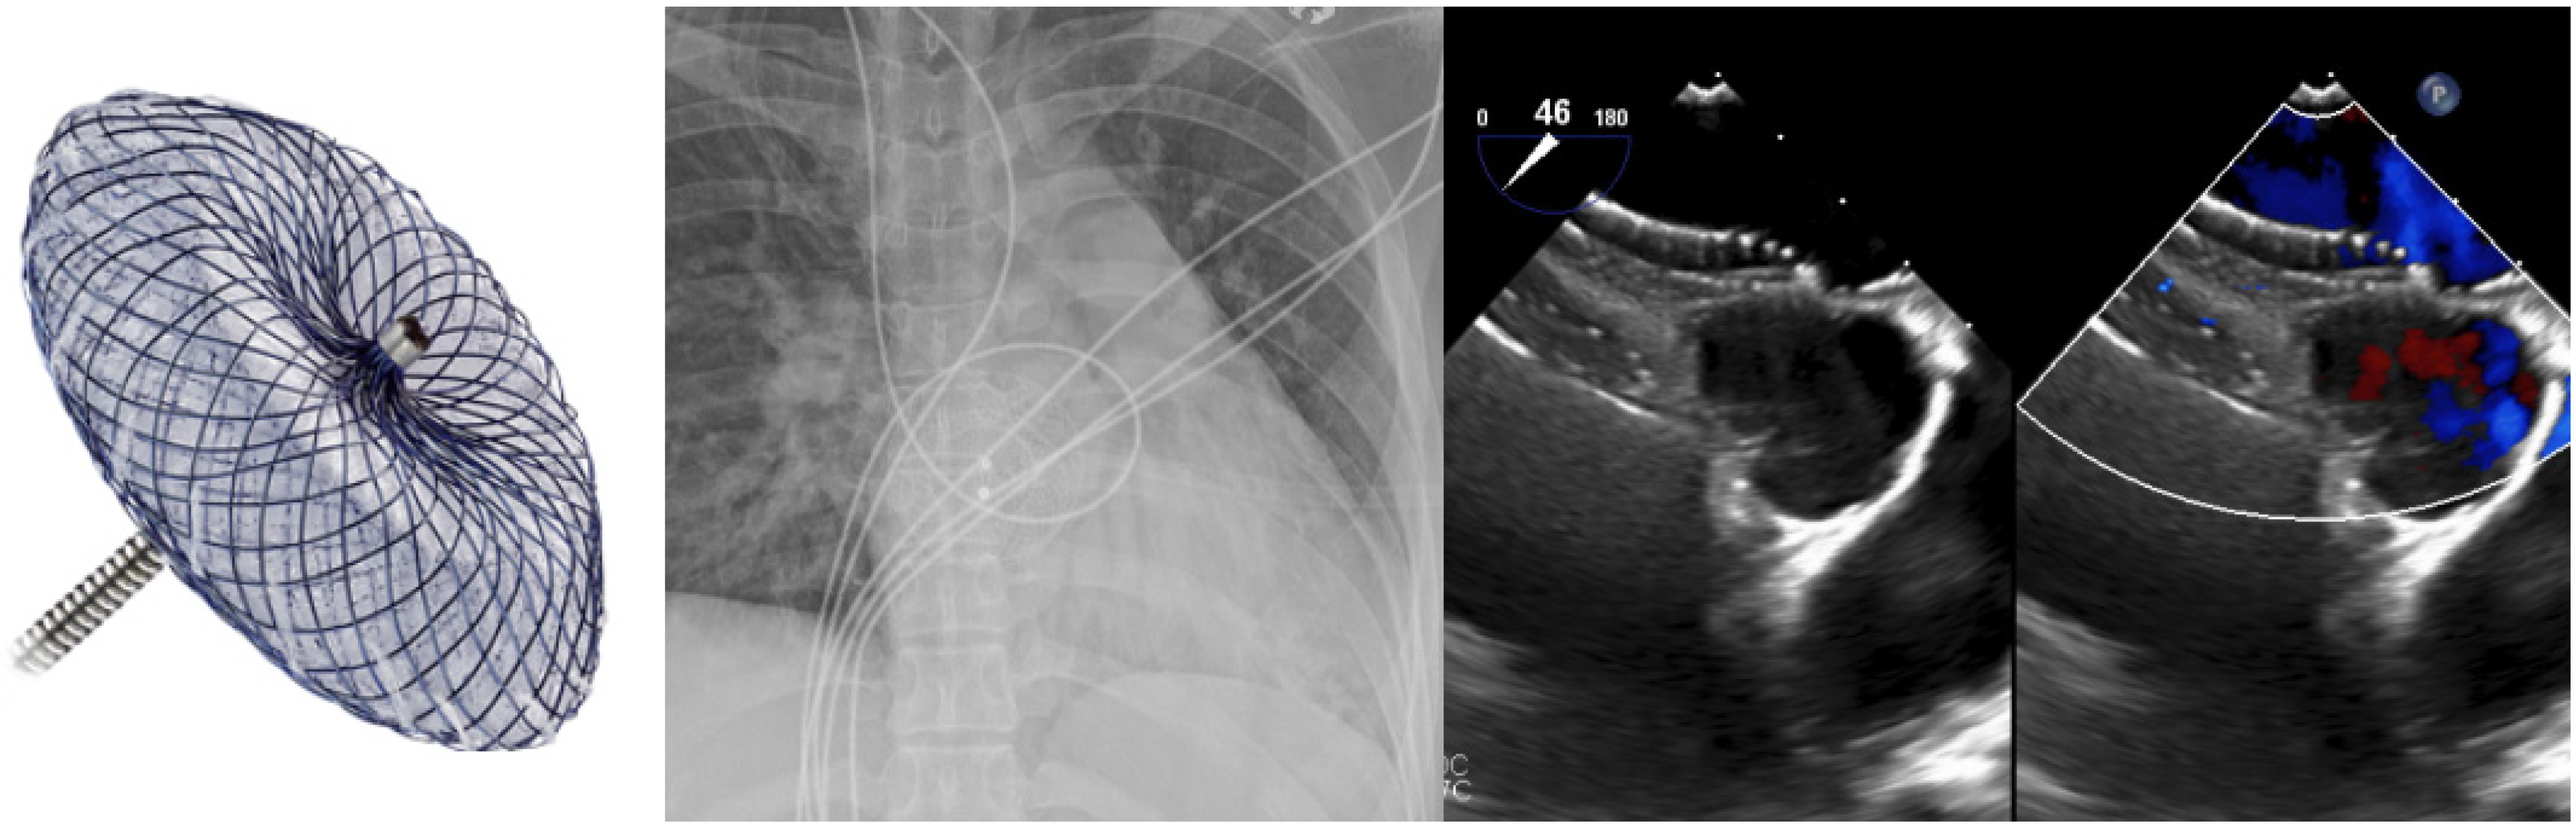

2. Ostium Secundum ASD Closure

5. VSD Closure